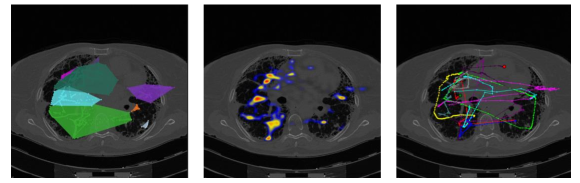

2.2 Step 1: A graph representation of the eye-tracking data

An example of eye-tracking data recorded from two cancer screening tasks is shown in Fig. 3 and Fig. 4. For each experiment, 2D images are overlaid with the coverage area (left), heatmap (middle), and scanpaths (right) representations inferred from the gaze patterns. Once gaze patterns are recorded, they are dense, hence, difficult to analyze (See Fig. 5). The aim in data sparsification is to represent the data with far less parameters and without significantly losing its content. It is also desirable to process the data easily and efficiently when sparisified. To end this, we propose to represent eye-tracking data as a graph and reduce its size without distorting the topology of the data structure by utilizing clustering and sparsification algorithms.

In the lung cancer screening experiments, our participants examined volumetric chest CT scans and the corresponding data was recorded in 3D space. The qualitative results and comparison of visual search patterns of the three radiologists are reported in Fig. 9. Each column shows one step of the proposed algorithm and each row corresponds to a radiologist. As can be seen, dense graphs hardly reveal any comparisons between radiologists’ visual search patterns. However, it is much easier to use sparsified graph (last column) for a global comparison of visual search pattern.

For a qualitative visualization on the image space (CT lungs), we showed the effect of our sparsification method on the dense eye-tracking data as well. Figure 10 shows the original gaze points, from radiologists, on the volume renderings of corresponding lung images in the first row. The second row illustrates the timing component of visual search patterns on the whole scan as well as the selected regions (i.e., attention region is indicated by circles) for each radiologist. The third row shows sampled data points after the clustering algorithm is applied. This figure supports how successful a very dense data can be sparsified for any local/global image analysis task easily.